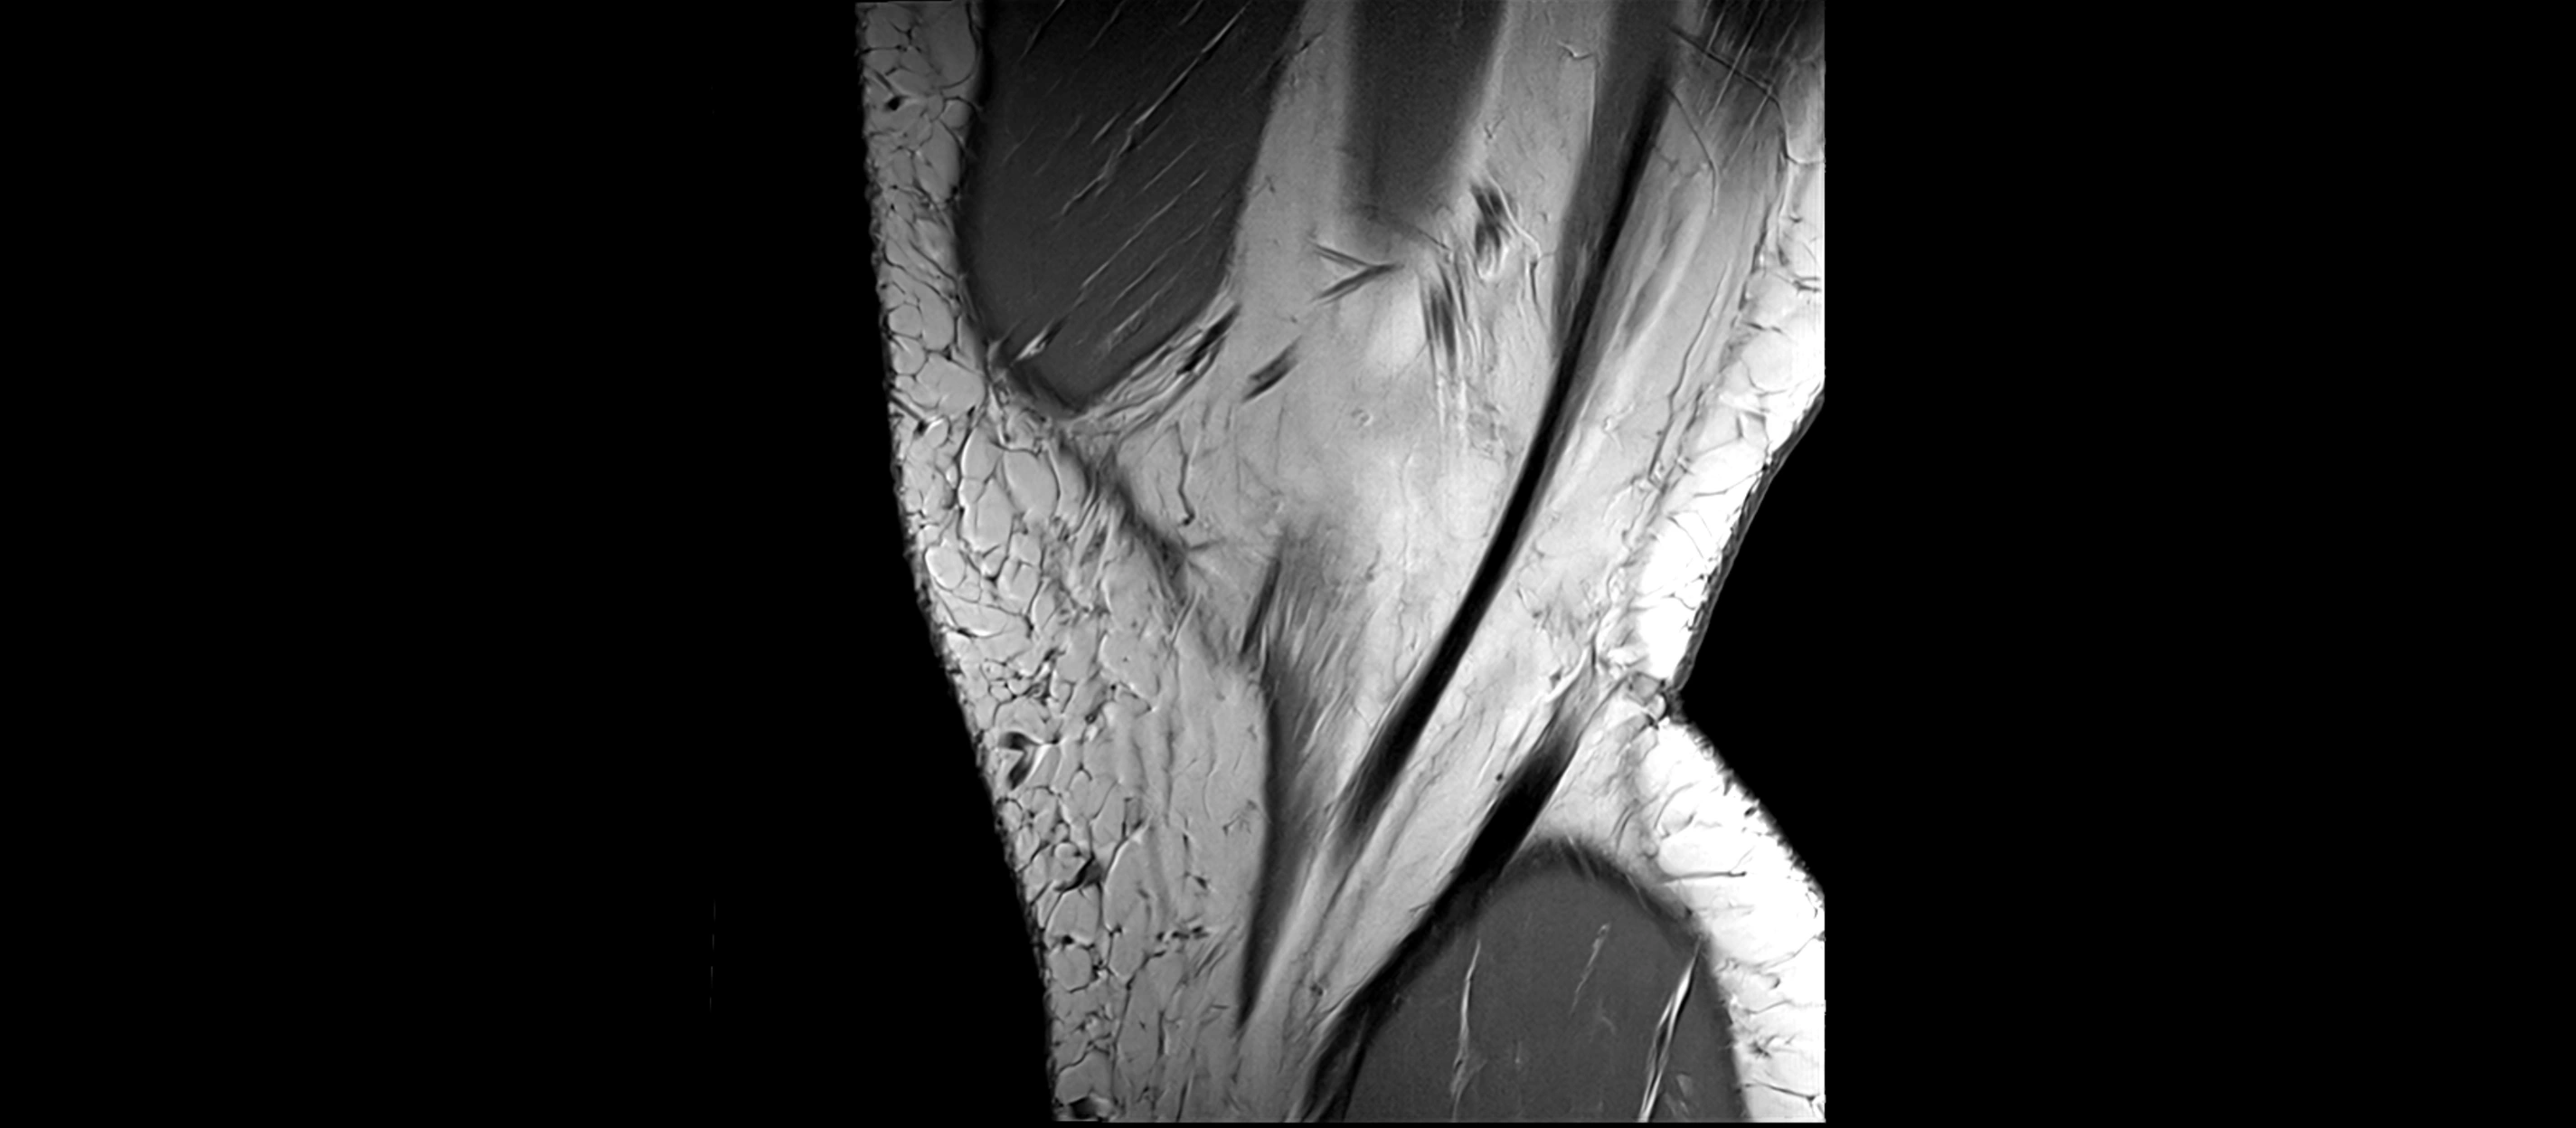

MRI Appearance

T1-weighted images:

• Normal ACL appears as a low-signal band-like structure crossing the intercondylar notch

• Surrounded by intermediate signal synovial fluid and fat planes

T2-weighted images:

• Normal ACL remains low signal

• Partial or complete tears appear as discontinuity, increased signal, or fiber laxity

MRI images

image